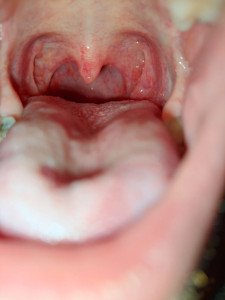

Сильная боль в горле и краснота

Здравствуйте болею третий день гриппом.

Сначало была температура 38.8

Я ее сбил анвимаксом.Но сильно болит горло и красное.Принимал дорьримицин не помогает.Что посоветуете принимать ещё?Фото горла прилагаю.